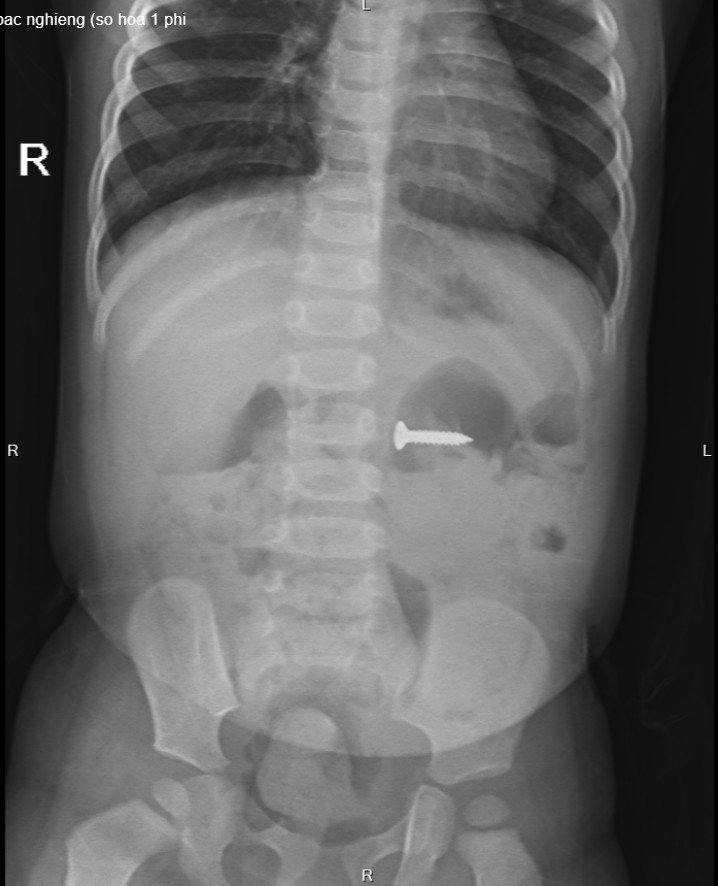

Tại Bệnh viện Sản Nhi tỉnh Phú Thọ, các bác sĩ chỉ định cho bé chụp X-quang thăm dò và phát hiện dị vật đinh vít sắc nhọn kích thước 2cm trong dạ dày, vị trí ngang đốt sống D3 của trẻ. Sau khi hội chẩn với các bác sĩ khoa Ngoại nhi tổng hợp và giải thích với gia đình, bệnh nhi được chỉ định gây mê nội soi tiêu hóa cấp cứu gắp dị vật.

Chiếc đinh vít sắc nhọn nằm trong dạ dày bệnh nhi trên phim chụp X-quang